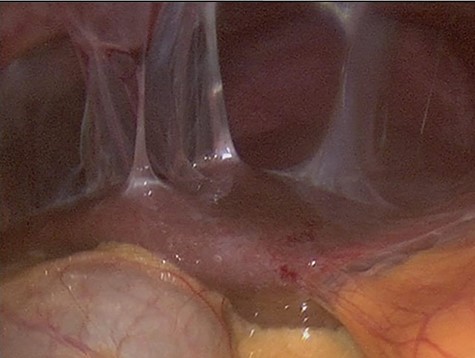

The decision to conduct a colonoscopy was undertaken to exclude inflammatory bowel disease and lower gastrointestinal (GIT) pathology. Colonoscopy revealed several adhesions throughout the pelvic organs (Fig. 1) and a biopsy revealed blunting of villi with subsequent crypt hyperplasia with no crypt abscesses, fistulas or granulomas (Fig. 2). There was a high clinical suspicion of celiac disease and laboratory confirmation was ordered. Lab results: positive immunoglobulin A (IgA) anti-tissue glutaminase 4.6 and immunoglobulin G (IgG) antideamidated gliadin peptide antibodies, IgA tTG 167 U/ml. Laparoscopy was performed as well to exclude any hidden etiologies including gynecological disorders that can lead to the adhesions but was not able to identify the cause.

Colonoscopy revealed several adhesions throughout the pelvic organs.

After the restriction of gluten-containing diet the GIT symptoms, pelvic pain and follow-up CT scans showed a significant improvement, and a follow-up colonoscopy showed no more adhesions ensuring a complete recovery of the patient. Figure 3 confirms the relationship of celiac disease and intra-abdominal adhesions.